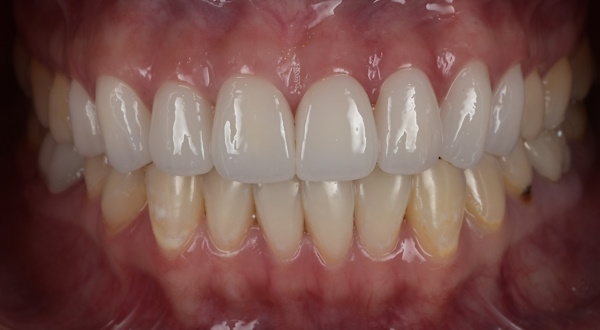

セラミック治療の治療例です。「以前、他院で治療した前歯の被せものの色味が不自然で気になる。また、被せものを入れてから歯茎が腫れるようになった。」とのことでご相談に来院されました。口腔内を確認したところ、セラミックの色が周囲の歯と調和しておらず、歯と歯茎の境目(マージン)部の適合が十分でないため、歯茎の炎症が起きている可能性が考えられました。当院にて、装着されていたセラミックの被せものを一度外し、歯茎の状態を確認したうえで、周囲の歯と自然になじむ色調のセラミックの被せものを新しく作り直しました。治療後は歯茎の腫れも落ち着き、前歯の色も周囲の歯となじみ、自然な見た目になりました。

治療後